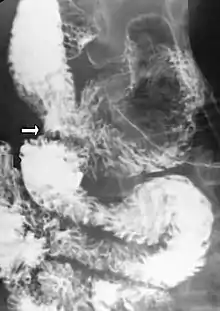

Diagnosis is can be difficult, and usually one of exclusion. SMA syndrome is generally considered only after people have undergone an extensive evaluation of their gastrointestinal tract including upper endoscopy, and evaluation for various malabsorptive, ulcerative and inflammatory instestinal conditions with a higher diagnostic frequency. Diagnosis may follow X-ray examination revealing duodenal dilation followed by abrupt constriction proximal to the overlying SMA, as well as a delay in transit of four to six hours through the gastroduodenal region. Standard diagnostic exams include abdominal and pelvic computed tomography (CT) scan with oral and IV contrast, upper gastrointestinal series (UGI), and, for equivocal cases, hypotonic duodenography. In addition, vascular imaging studies such as ultrasound and contrast angiography may be used to indicate increased bloodflow velocity through the SMA or a narrowed SMA angle.[13][14]

Upper gastrointestinal series showing extreme duodenal dilation (white arrow) abruptly preceding constriction by the SMA.- Ultrasound showing SMA syndrome[19]